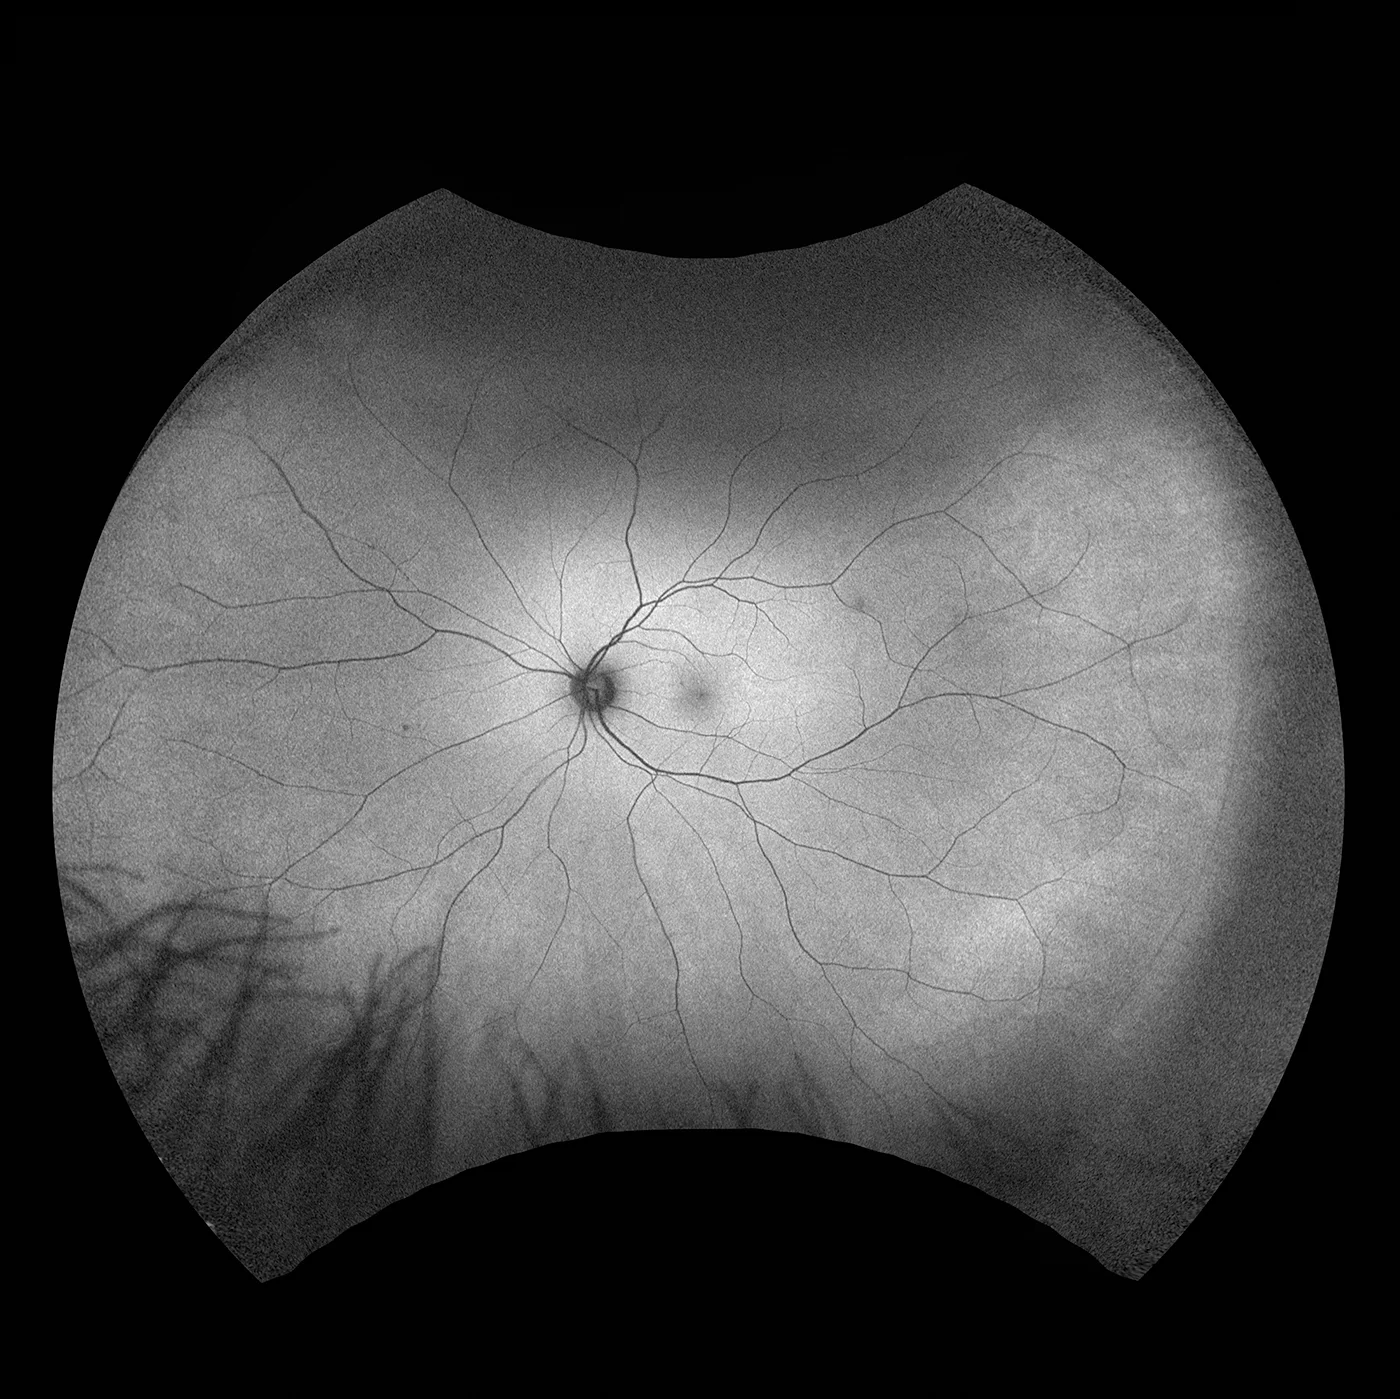

Optos a développé l'imagerie rétinienne dotée d'une technologie de laser à balayage ultra-grand champ (UWF™) afin d'obtenir une photographie du fond d'œil qui aide les praticiens à diagnostiquer, analyser, documenter et suivre les pathologies oculaires susceptibles d´être présentes en premier lieu dans la périphérie. Sans la technologie UWF™, les pathologies de la périphérie peuvent passer inaperçues lors de l’utilisation des techniques d’examen et des équipements traditionnels. Optos propose plusieurs appareils d'imagerie ultra-grand champ à haute résolution, générant des images simultanées sans contact allant du pôle à la périphérie pour visualier plus de 80 % ou 200˚ de la rétine en une seule prise, sans désagrément pour le patient.

California

Notre appareil le plus apprécié, California, a été développé pour l'imagerie médicale et constitue une référence pour les programmes de dépistage rétinien. California est disponible avec plusieurs options de modalités d'imagerie. California produit une image rétinienne de 200° en une seule prise d'une précision inégalée en moins d’½ seconde, qui transforme la prise en charge des pathologies, notamment pour la RD, Atrophie Géographique, la DMLA et l'uvéite.